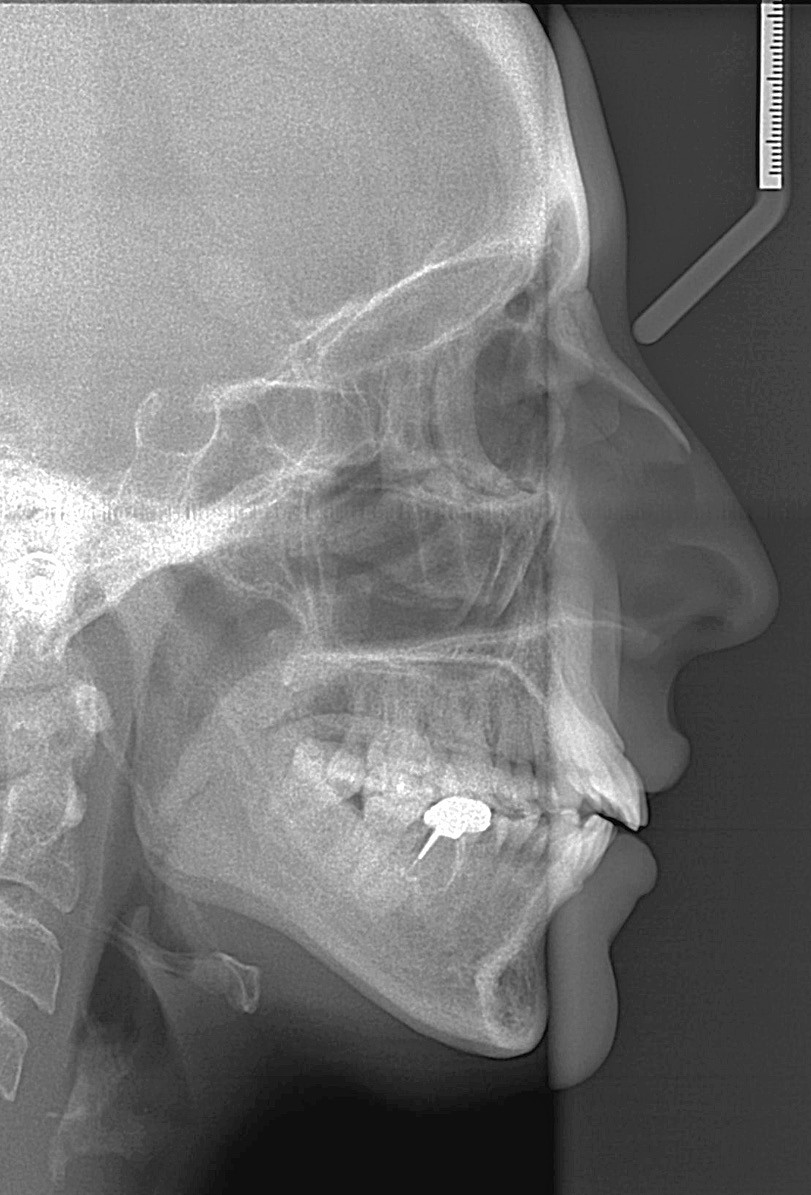

C’est précisément le cas de cette patiente de 33 ans qui présente une classe II squelettique par rétrognathie mandibulaire sur un schéma vertical hyperdivergent associée à une classe II/1 dentaire avec DDA par excès et biproalvéolie. Son profil est convexe, cis-frontal et, sur le plan fonctionnel, on peut observer une dysfonction linguale et une incompétence labiale au repos. Il en résulte une contracture des muscles de la sphère péri-orale lèvres jointes. La formule dentaire n’est pas complète puisque les quatre deuxièmes prémolaires ont été extraites lors d’un premier traitement orthodontique et qu’il y a également agénésie des troisièmes molaires 18 et 38 (fig 1 à 11).

Au regard de ces éléments, la décision thérapeutique choisie intègre une prise en charge orthodontique associée à une chirurgie orthognathique d’avancement mandibulaire et à une mentoplastie. L’étape initiale du traitement orthodontique consiste en la levée des compensations dentaires qui se traduit par la correction de la proalvéolie mandi– bulaire dans le but de pouvoir corriger la classe II squelettique et dentaire par avancement chirur- gical de la mandibule. Pour cela, des mini-vis d’ancrage sont positionnées distalement aux secteurs 3 et 4, enfouies à la base des branches mandibulaires avec des chaînettes métalliques émergentes dans la cavité buccale. L’objectif est d’assurer le repositionnement incisif mandibulaire grâce à des modules élastiques.